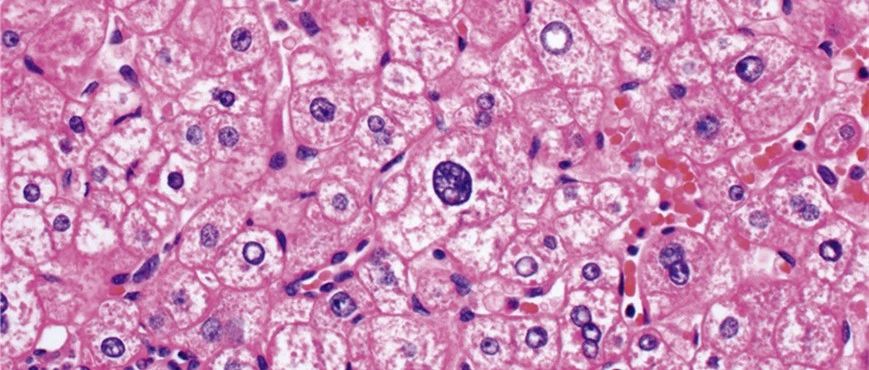

好文分享|形态与分子结合诊断的典范-肝细胞腺瘤(二)

一肝细胞腺瘤诊断要点肝细胞腺瘤为细胞学非典型轻微或缺失的高分化肿瘤。高倍镜下,瘤细胞与背景肝细胞的形态几乎一致。炎症性腺瘤中常见散在的轻度细胞核增大,但核浆比仍接近正常,且细胞核为圆形,细胞核轻度深染。图1.肝细胞腺瘤,本例几乎无细胞学非典型,但核浆比稍有升高(上);同一病例中的背景肝脏组织学表现见下图。图2.本例为炎症性肝细胞腺瘤,散在轻度细胞学非典型,个别瘤细胞的细胞核较大、深染,但核浆比一般仍保持正常。...

华夏病理网 2023-01-04